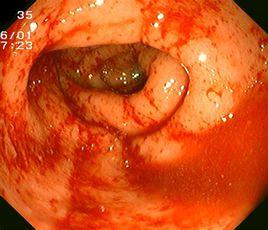

治療直腸炎,首重檢查,因此,在檢查上,長沙肛泰肛腸醫院引進了新一代日本奧林巴斯無痛腸鏡,可全面檢查整個腸道,以特有的六大優勢成為檢查的金標準。

二、 高清晰度:一切病變組織在高解析度的鏡頭下無所遁形,連細微的毛細血管都看得清清楚楚;

五、 視野開闊:小則細察毛細血管之微,大則環視整個腸管概況,伸縮自如;